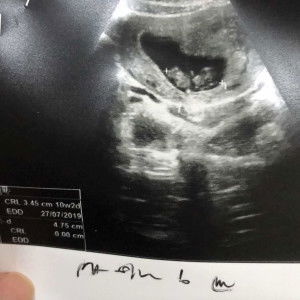

Positif ke nie mommies? masih tertanya tanya.

Positive !